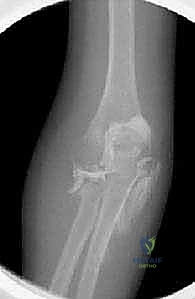

2. التصوير الشعاعي (X-Rays)

هو الخطوة الأساسية لتأكيد الكسر. يتم التقاط صور من زوايا متعددة (أمامية خلفية، وجانبية، ومائلة).

* علامة وسادة الدهون (Fat Pad Sign / Sail Sign): في بعض الأحيان، خاصة في كسور النوع الأول غير المزاحة، قد لا يظهر خط الكسر بوضوح في الأشعة. في هذه الحالة، يبحث الدكتور هطيف عن "علامة الشراع" أو ارتفاع وسادة الدهون المحيطة بالمرفق في الصورة الجانبية، والتي تدل على وجود نزيف مفصلي (Hemarthrosis) يؤكد وجود كسر خفي.

2. الرد المفتوح والتثبيت الداخلي (ORIF - Open Reduction and Internal Fixation)

تُستخدم للبالغين في الكسور المزاحة التي يمكن إنقاذها. يقوم الدكتور هطيف بإجراء شق جراحي دقيق للوصول إلى الكسر، ثم يقوم بإعادة ترتيب القطع العظمية بدقة متناهية (مثل تجميع قطع اللغز)، وتثبيتها باستخدام مسامير صغيرة جداً (Headless compression screws) أو شرائح معدنية تشريحية مصممة خصيصاً لرأس الكعبرة. الهدف هو توفير تثبيت قوي بما يكفي للسماح للمريض بتحريك مرفقه في اليوم التالي للجراحة.